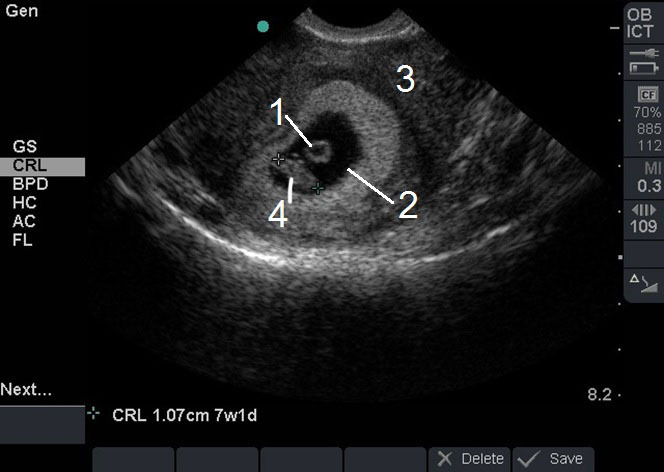

Pelvic Transvaginal (TV) Intrauterine Pregnancy (IUP) with Crown Rump Length (CRL) 7Wk-1D Image

1. Yolk Sac

2. Gestational Sac

3. Uterus

4. Fetal Pole